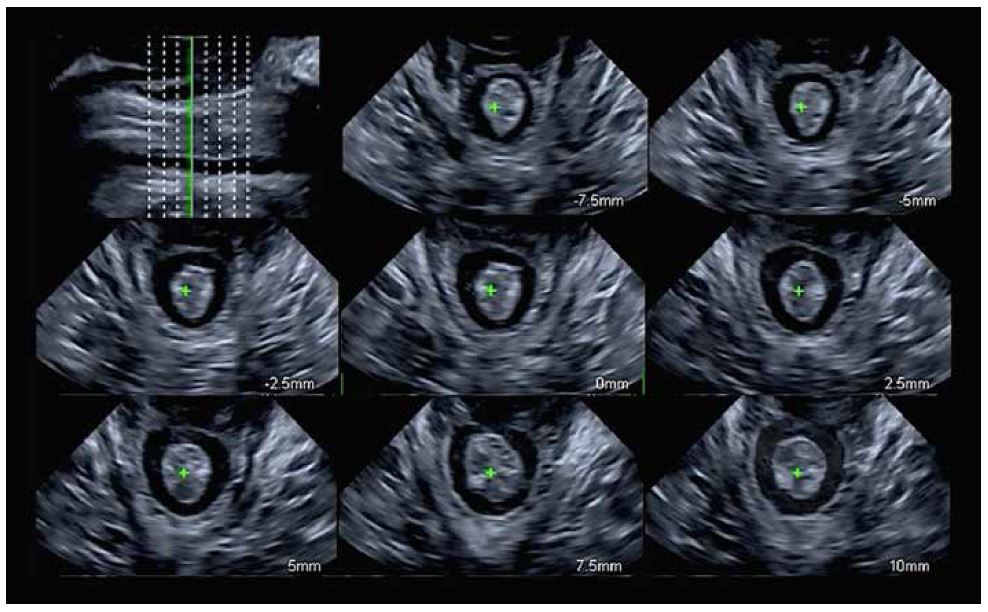

Мультиплощинна реконструкція з площини мінімальних гіатальних розмірів (мал. 10) є стандартизованим і еталонним способом оцінки авульсії LAM. Осьові площини отримують з інтервалом 2,5 мм (5 мм каудально і 12,5 мм краніально), оцінюючи загалом 8 площин (мал. 11). Точне розташування 8 площин встановлюється по трьох центральних площинах (жовта пунктирна лінія на мал. 11):

• 1st прощина (зліва): дуги лобкового симфізу розділені.

• 2nd площина (центральна): дуги лобкового симфізу зімкнуті.

• 3rd площина (справа): лобок не повинен відображатися, заміняючись акустичною тінню.

Малюнок 10. Площина мінімальних розмірів діафрагми. P: Лобок, U: Уретра, V: Піхва, AC: Анальний отвір, LAM: М'яз-підіймач відхідника

Малюнок 11. Багатоплощинна реконструкція м'язу-підіймача відхідника (LAM) з трьома центральними площинами, виділеними жовтим.

Авульсія LAM визначається як відшарування м'яза від лобкової області. Воно є повним, коли воно присутнє в трьох центральних площинах, і частковим, коли є пошкодження м’язів в інших площинах без відповідності критеріям повного відриву.